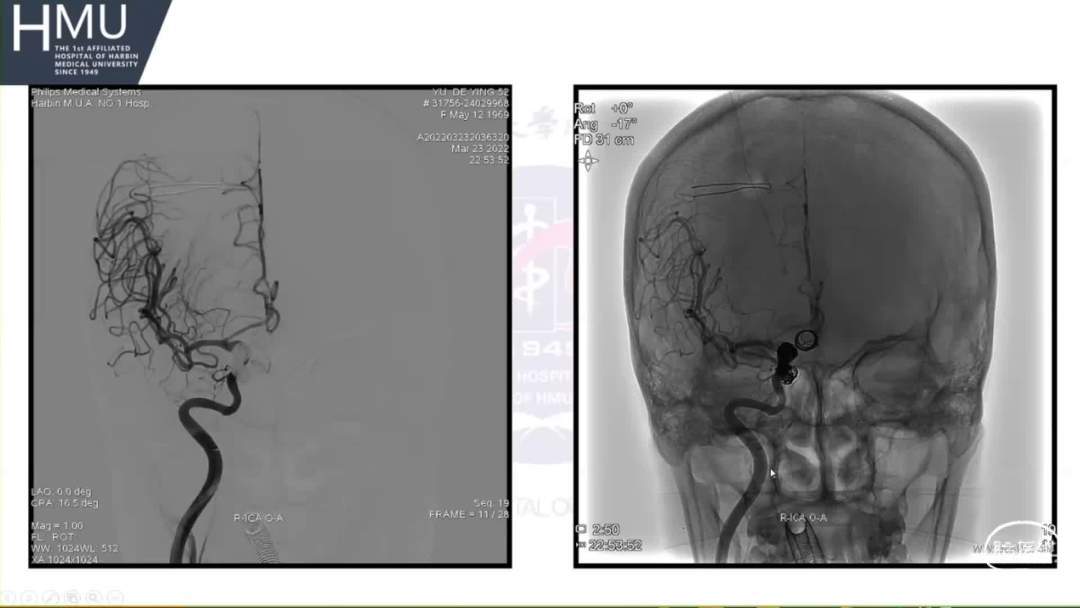

21:00覆膜支架置入术

海绵窦段动脉瘤如何导致蛛网膜下腔出血?